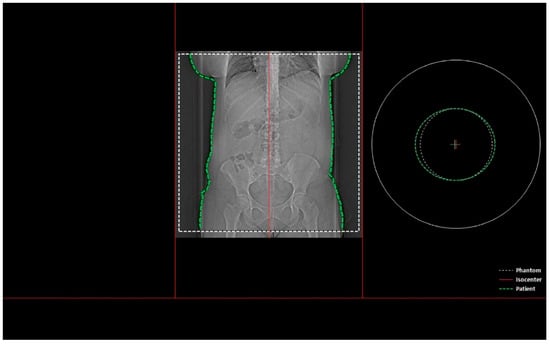

- Whether the patient was in the isocenter—Figure 1 shows the patient outside the isocenter, while Figure 2 shows the patient inside the isocenter.

Figure 2. Image from the Dose&Care system showing patient placement in the isocenter.